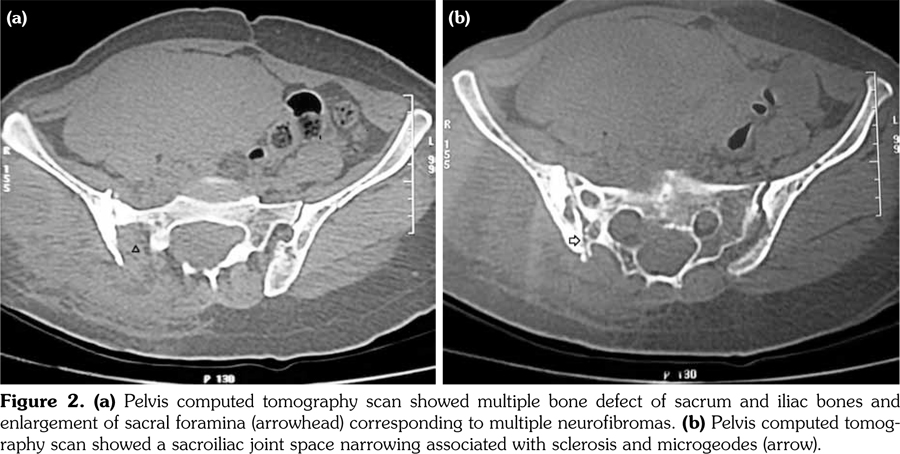

The radiographic exam of the pelvis pointed out a condensation of the right sacroiliac joint reflecting unilateral sacroiliitis (Figure 1). Osseous defects of the sacrum, iliac bones, and right femur were also noted. Pelvis computed tomography scan showed a sacroiliac joint space narrowing associated with sclerosis and microgeodes which might suggest a septic sacroiliitis, particularly of tuberculous or Brucella origin. Multiple bone defects of the sacrum and iliac bones and enlargement of sacral foramina corresponding to multiple neurofibromas (Figure 2) were also noted. Magnetic resonance imaging revealed a juxtaarticular plexiform neurofibroma with massive invasion of the right sacroiliac joint and soft tissue (Figure 3). Tuberculous origin and malignant transformation were both discussed. Sacroiliac biopsy was performed showing histological patterns consistent with NF, with fusiform cells and fibrillary cytoplasm making a typical lemuroid appearance. Patient was referred to surgery.